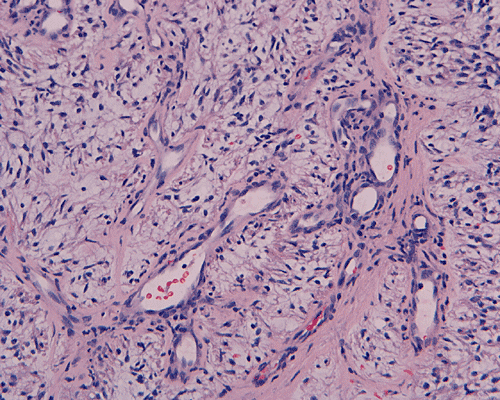

In a substantial amount of area, the tumor is composed of spindle cells with prominent perivascular arrangment and microcyst formation (Panel A and B). These vessels are surrounded by a thin rim of bipolar spindle cells (Panel C). The paucicellular perivascular mantle that is typical for ependymoma is absent in these perivascular arrangements. Adjacent to these perivascular arrangment is substantial amount of myxoid changes. On high-magnification, the tumor cells appear bland in histology, bioplar and spindle in shape, and admixed with a large amount of myxoid substance (Panel D and E). There is a lack of mitosis or significant pleomorphism. In some areas, the tumor is composed exclusively of spindle cells in a myxoid background with microcyst formation but without perivascular coronary arrangement of tumor cells (Panel F). It is not uncommon to observe areas with spindle cells clinging to the blood vessels (Panel G). In a minority of areas, there is increase in cellularity (Panel H). Some vessels seem to be composed of glomeruloids of blood vessels with plump endothelial cells (Panel I).

Histologically, the salient features of PMA are rather monotonous, small, spindle bipolar cells with angiocentric arrangement within a strikingly myxoid background. The myxoid basckground material is positive for Alcian blue but negative for PAS 1, 3,.  These features are well illustrated in our case. Occasional necrotic foci and mitotic figures can be present. Atypical mitotic figures and substantial nuclear pleomorphism should not be seen. Occasionally, the tumor cells infiltrate the surrounding non-neoplastic brain parenchyma but neither the histological feature nor radiological features would suggest a diffusely infiltrating astrocytoma. In contrast to pilocytic astrocytomas, PMAs do not possess a true alternating densely packed-loosely packed biphasic pattern, do not contain eosinophilic granular bodies or Rosenthal fibers 1, 4. Development of features that are seen in pilocytic astrocytomas such as the biphasic pattern and Rosenthal fibers have been described by Fernandez et al 4. These features are uncommon at the initial presentation but they can develop after chemotherapy. Although these features may suggest maturation of the tumor after chemotherapy, no association with improved prognosis has been described in the study by Fernandez et al 4. The angiocentric arrangement of tumor cells is another trap as it would suggest ependymoma. However, these arrangements are more irregular and fibrillar than the perivascular rosettes in ependymomas.